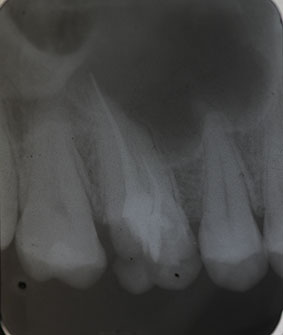

Patient N.M. wünscht eine Drittmeinung, zwischenzeitlich hatte er bereits einen zweiten Zahnarzt konsultiert. Dieser bestätigte eine insuffiziente Wurzelfüllung und vermutete eine Instrumentenfraktur im mb1 (Abb. 1).

Röntgenbefund

Mittels Röntgenaufnahme lässt sich ein frakturiertes Instrument in mb1 vermuten. Des Weiteren scheint es, als sei der distale Wurzelkanal sowie der mb2 nicht abgefüllt worden, was sich zu einem späteren Zeitpunkt der Behandlung bestätigen sollte. Der Patient wurde vom vorbehandelnden Zahnarzt über die Fraktur nicht aufgeklärt.